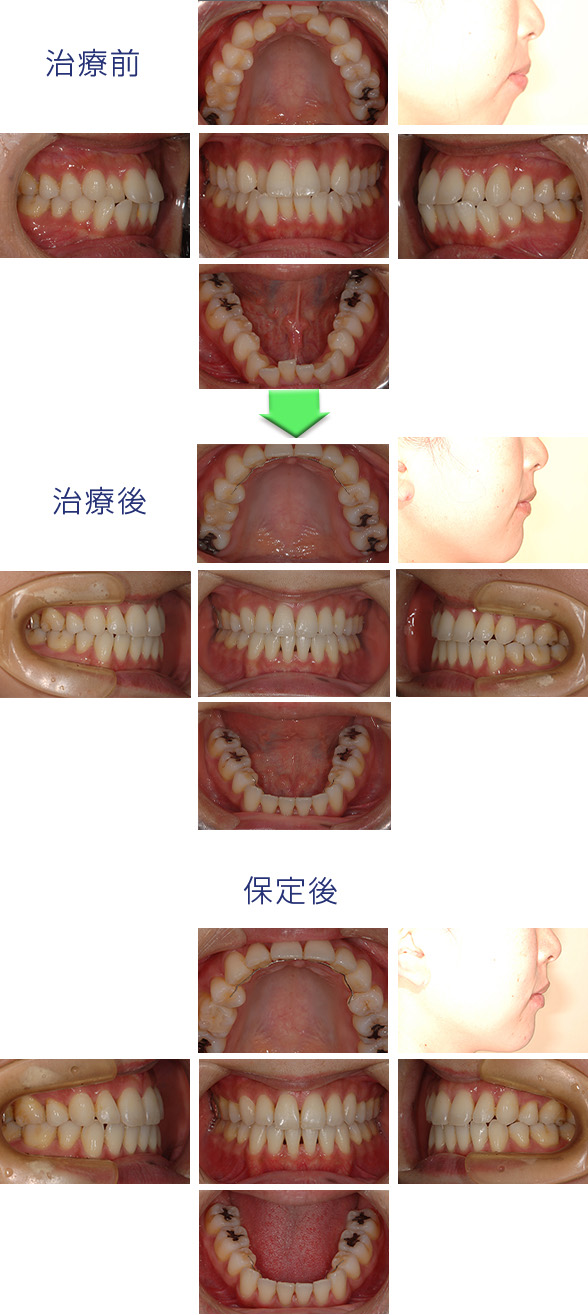

上下顎前突症の患者様でした。

初診時は上下の歯が前に出た状態です。さらにわずか歯の並びがデコボコしていました。

歯の出っ張りなくし、口元を美しくしたいとのことでしたので、上下の第一小臼歯を抜歯して矯正歯科治療を開始しました。治療後は口元が引っ込み、口が閉じやすくなり、横顔のバランスが良くなりました。従来はヘッドギア(在宅時に頭と口の中の矯正装置につける装置)などの患者様の協力が不可欠であったのがミニスクリューを使用することで患者様の負担を軽減して治療できるようになりました。

診断名:上下顎前突症

治療開始年齢:31歳

使用した装置名:マルチブラケット装置(ラビアル歯の表からの矯正)

抜歯:上下第一小臼歯

治療期間:1年10ヵ月

費用の目安:70万

リスクおよび副作用:大人の患者様にすべてに当てはまることですが、治療終了後のブラックトライアングルの出現(歯が整列すると隣り合う歯どうしに隙間ができること)。小さくすることができますが全くなくすことはできません。歯の長さが術後に伸びたように見える(矯正治療による歯肉の退縮)。ミニスクリューの脱落、その後再度植立は行えます。